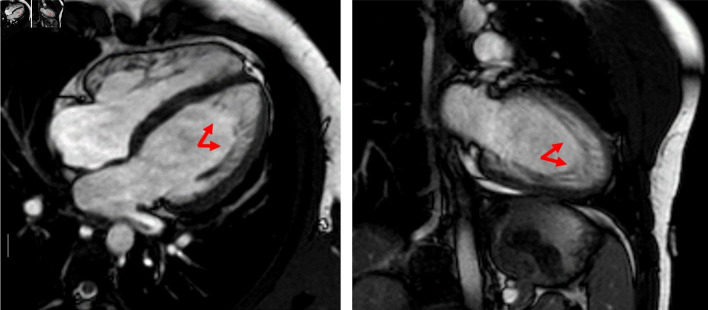

Left ventricular non-compaction (LVNC) is a rare primary cardiomyopathy with genetic etiology, resulting from an abnormality of myocardial development during embryogenesis. It carries an elevated risk of left ventricular dysfunction, thromboembolic events and malignant arrhythmias. We report the case of LVNC associated with paroxysmal atrial fibrillation and ankyrin 2 (ANK2) mutation at the genetic test. An 18-year-old competitive athlete visited our medical center to undergo the diagnostic investigations protocol preparatory to the release of the suitability for competitive practice. The echocardiographic examination shows LVNC without ventricular remodeling (left ventricular ejection fraction (LVEF) 53%, global longitudinal strain (GLS) -18.3%). The echocardiographic diagnosis was confirmed by cardiac magnetic resonance imaging (cMRI), which revealed dense hypertrabeculation in the left ventricular apex and lateral wall. The cardiogenetic investigation showed a c.9145C>T variant (p.Arg3049Trp) identified in the ANK2 gene. This mutation is associated in the literature with rare cases of LVNC. The patient underwent an extended Holter monitoring which excluded ventricular arrhythmic events but showed two brief episodes of paroxysmal atrial fibrillation. Despite the absence of significant ventricular remodeling, considering the presence of paroxysmal atrial fibrillation and the presence of a mutation in the ANK2 gene, which has several variants related to high-risk phenotypes, it has been decided to suspend the competitive practice, and is defined an adequate clinical-diagnostic follow-up.